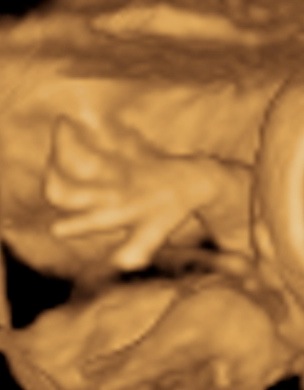

A 3D-s babafotok meg mindig lenyugoznek, nem birok betelni veluk. SZomoruan olvasom, hogy mennyi aprobb-nagyobb kellemetlensegetek van, de szerintem mindenki nagyon szuperul halad, ugyesek vagytok...le a kalappal foleg a dolgozok, vagy mar babasok elott! majd most teszek fel kepeket es is Azzurrarol, bar mar tobb, mint 5 hete keszultek, de ujabbak mar nem lesznek, es mivel kimaradtam abban az idoszakban, most potolom. Az tuti, hogy ezentul mindenkinek javasolni fogom a 4D-t ilyen koran is (22+1 hetesen voltunk), mert bar csimota ducibb volt az atlagnal es mar akkor volt rajta jo adagnyi izom (ez is a napi 1 l tej

), de egy sovanyabb baba is csodaszep szerintem...mindent el lehet mondani, csak azt nem, hogy csontkollekciok lennenek. Osszessegeben ugy nez ki, hogy ram hasonlit, de a szemoldokcsontja es a szaja az egy az egyben a parome...szerencsere...neki az sokkal szebb...remelem, haj-ugyben is ra ut majd